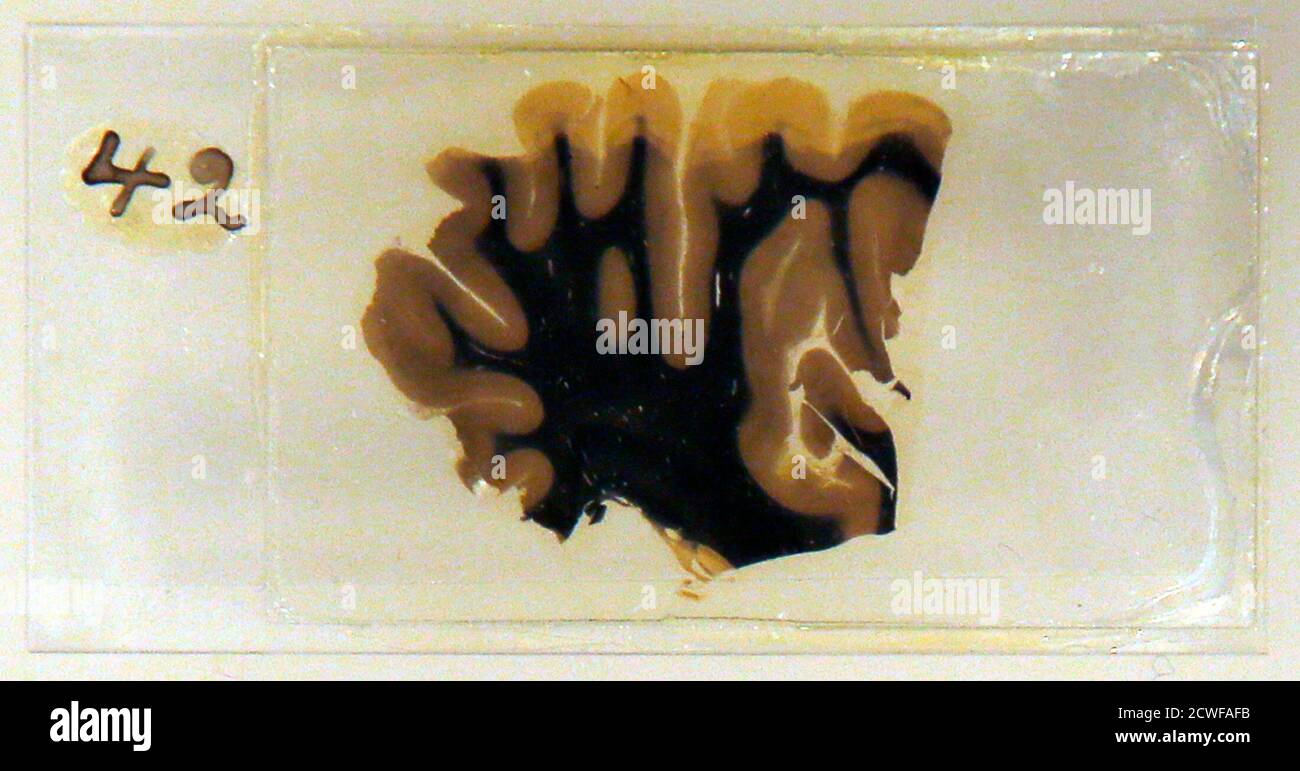

Https www alamy com a specimen of nobel physicist albert einsteins brain is seen in a glass slide at an exhibition at the wellcome collection in london march 27 2012 weve pickled it dessicated it drilled it mummified it chopped it and sliced it over centuries yet as the most complex entity in the known universe the human brain remains a mysterious fascination with samples of albert einsteins preserved brain on slides and specimens from other famous and infamous heads such as the english mathematician charles babbage and notorious mass murderer william burke an exhibition opening in london this week image377121679 html (Dateityp jpg)